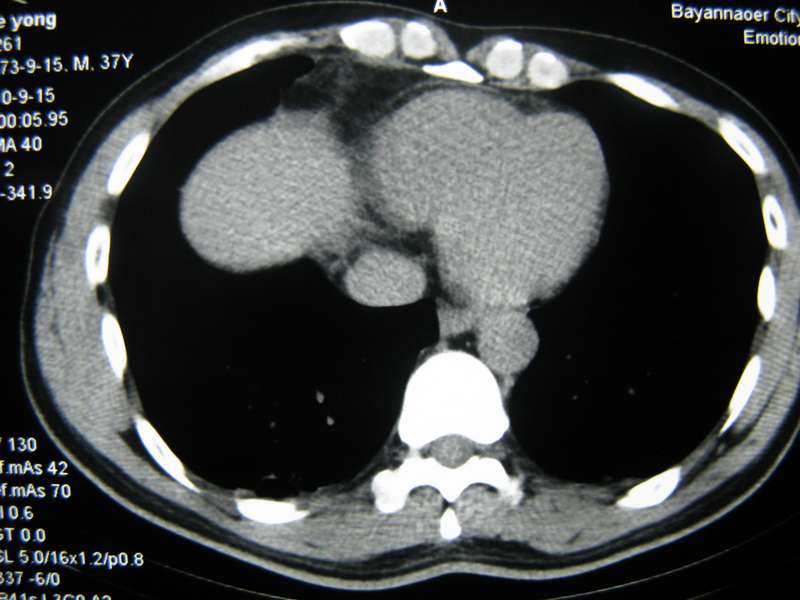

男,37岁,主述胸疼厉害,无咳嗽,无发热,血象也不高,病灶内ct值脂肪密度,右侧胸腔内少量积液,同道们考虑什么?谢谢!

脂肪垫,右下肺感染,少许积液是症状所在

纵膈脂肪堆积,右肺慢性炎症。

两肺下叶基底段纤维灶,右肺下叶基底背侧相应胸膜肥厚,右肺中叶内侧段部分不张。前中下纵隔团块状脂肪影,随访除外胸腺脂肪瘤。

纵膈脂肪堆积,右肺慢性炎症

脂肪垫;右肺慢性炎症。

不除外膈疝。